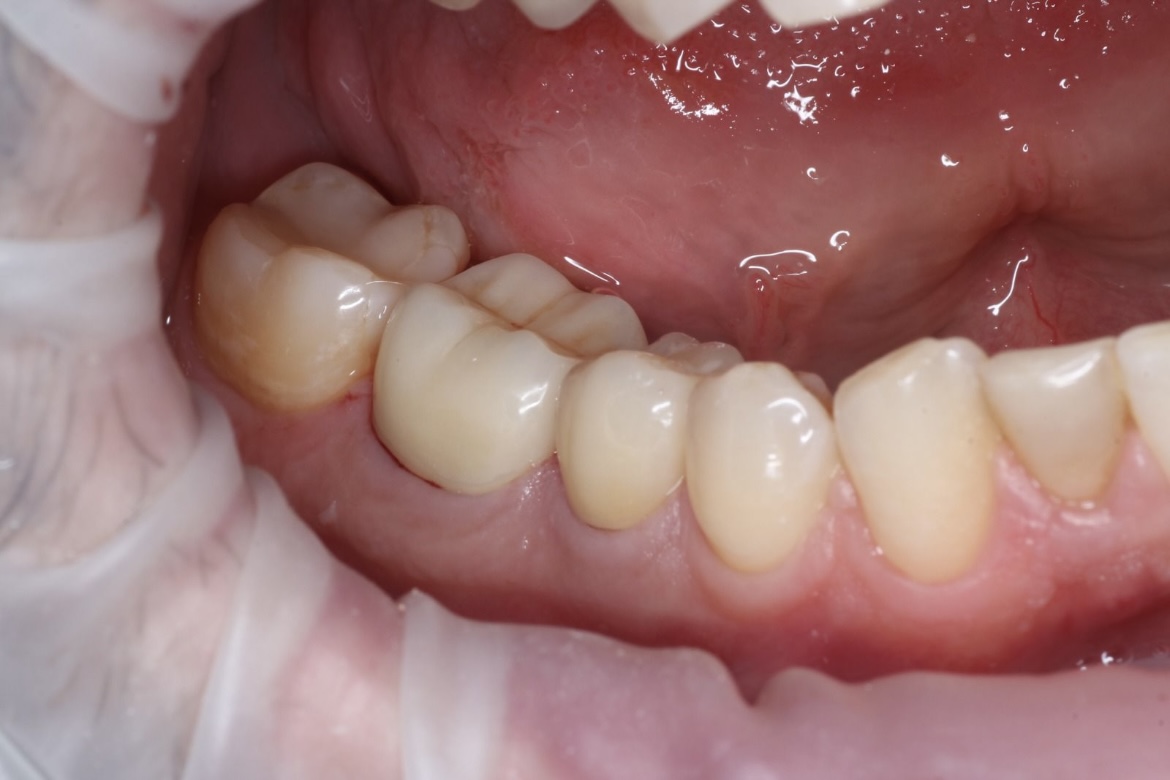

Наши работы